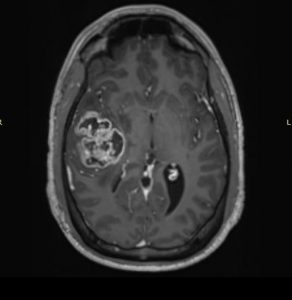

Χωροκατακτητική Εξεργασία δεξιού Κροταφικού Λοβού